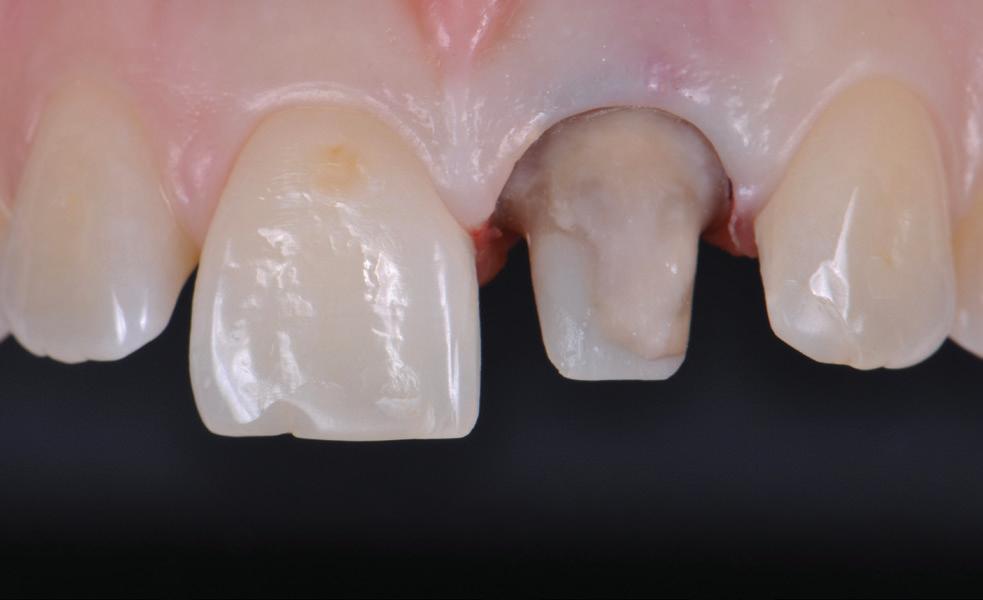

Figure 4. Maxillofacial surgery. Figure 6. TMJ analysis. Figure 8. Airway analysis. Figure 10. Periodontics. Figure 5. Orthodontics. Figure 7. Implant placement. Figure 9. Prosthodontics. Figure 11. Endodontics.